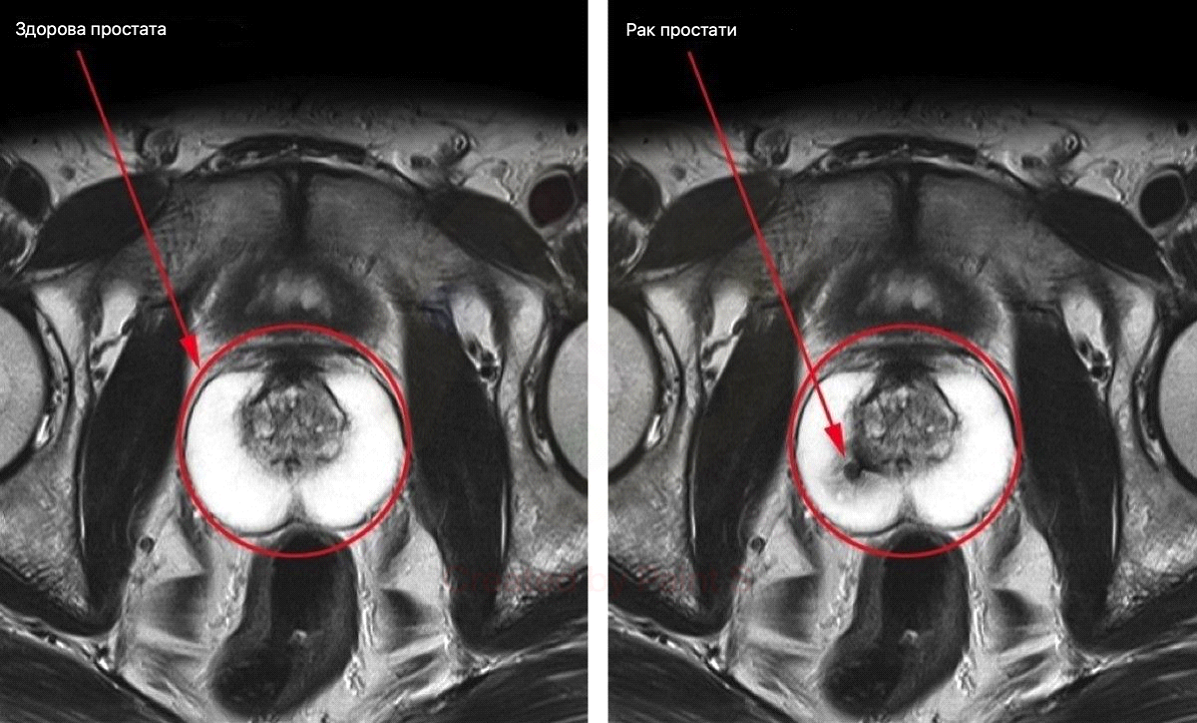

За статистикою, 63% українських чоловіків старше 35-40 років мають проблеми з сечовипусканням і потенцією, які є основними симптомами запущеного простатиту. У решти - простата також не в порядку, але до характерних симптомів поки не дійшла. За тією ж статистикою медиків, патологічні процеси в простаті (в тій чи іншій мірі) спостерігаються у 98% українських чоловіків старше 35-40 років.

Сам по собі простатит - це пряма дорога спочатку до аденоми простати, а потім до імпотенції та раку. Проблема ускладнюється ще тим, що лікування від простатиту складне і тривале. Необхідно приймати велику кількість антибіотиків і пройти курс масажу простати (лікар через анальний отвір пальцем масажує пацієнтові простату щодня протягом 2 тижнів). Але навіть при успішному лікуванні простатит в 87% випадків повертається знову протягом 1 року.